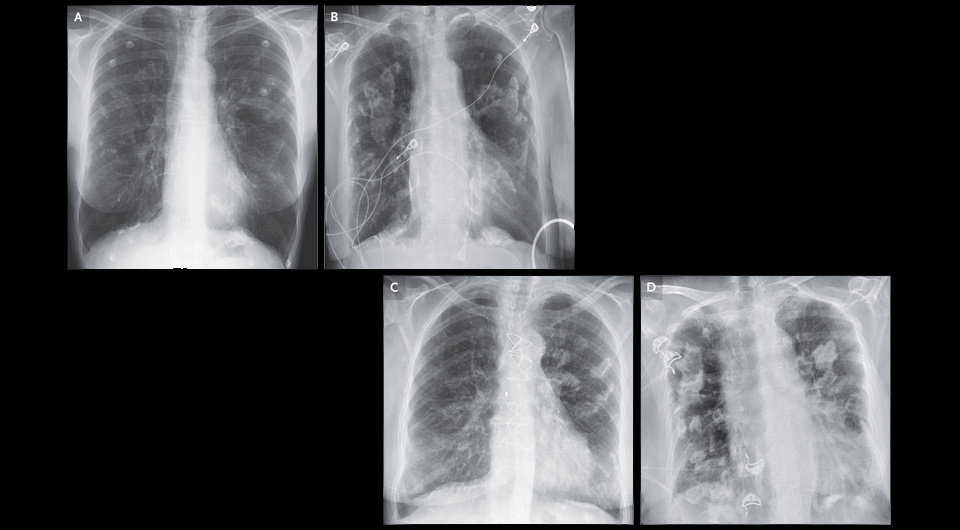

В американскую больницу поступила 80-летняя женщина с обострением хронической обструктивной болезни легких. В анамнезе у нее был стаж курения 40 пачко-лет и вторичный контакт с асбестом в детстве — она с двумя сестрами играла с отцом, который приходил с работы по установке теплоизоляции в одежде, покрытой похожими на снег частицами. При аускультации легких определялись рассеянные влажные хрипы без свистящих. На рентгенограмме и компьютерной томограмме визуализировались плевральные бляшки с кальцинатами с обеих сторон, значительно более выраженные, чем на снимке 20-летней давности. Врачи Шон Чиллаг (Shawn Chillag) и Ричард Скотт Морхед (Richard Scott Morehead) из Научно-медицинского центра Университета Западной Виргинии поделились этим случаем в New England Journal of Medicine.

Shawn Chillag, Richard Scott Morehead / NEJM, 2024